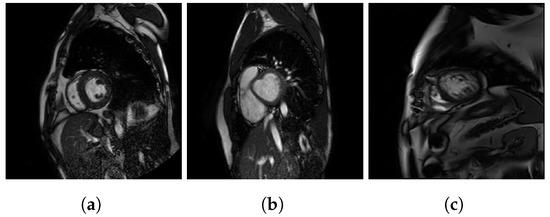

A sample image of each dataset is showed in Figure 2. The differing results shown in Table 1 are due to the fact that the P dataset has more images than X and H combined, but also that these datasets are intrinsically different as:

Figure 2.

Sample images of each dataset: (a) P dataset, (b) X dataset, and (c) H dataset.